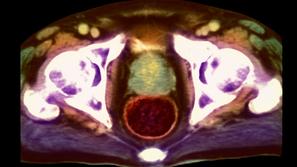

Rak prostate

Rak prostate: Čakanje na operacijo je mučno in neprijetno

V Sloveniji umre 380 oseb zaradi raka prostate, letno jih zboli 1300.